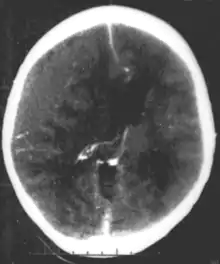

Nontraumatic epidural hematoma in a young woman. The grey area in the top right is organizing hematoma, causing midline shift and compression of the ventricle.

Nontraumatic epidural hematoma in a young woman. The grey area in the top right is organizing hematoma, causing midline shift and compression of the ventricle. Non-contrast CT scan of a traumatic acute hematoma in the right fronto-temporal area.